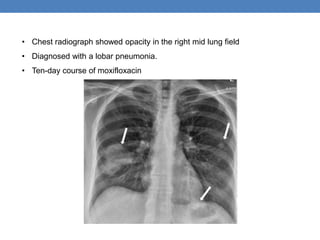

• Chest radiograph showed opacity in the right mid lung field

• Diagnosed with a lobar pneumonia.

• Ten-day course of moxifloxacin